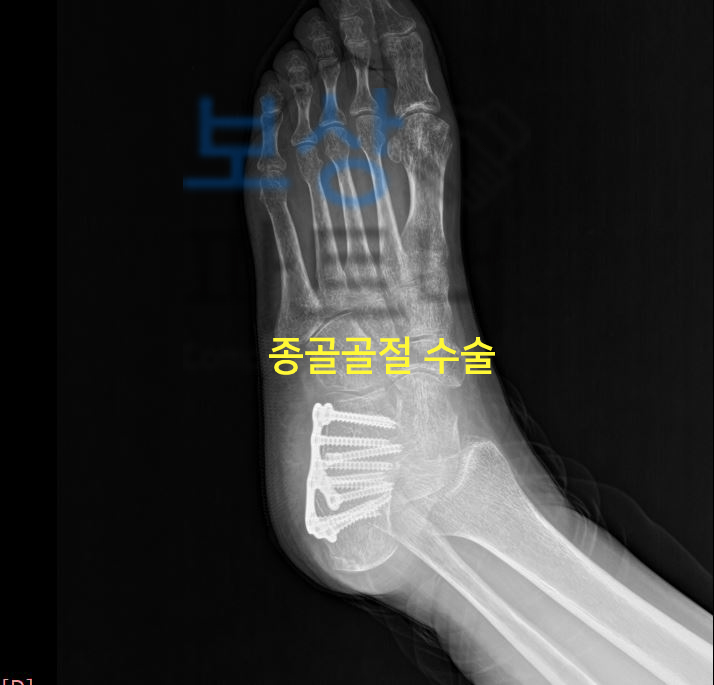

의료용 워커 허리 고관절 골절 인공관절 치환술 장해 사고로 인해 허리 골절, 고관절 골절, **발목 골절, 인공관절 치환술 **등등 위 진단 중 하나라도 해당 된다면 내 보험에서 상해 후유장해 보상 알아보셔야 합니다.

수술한지 얼마 되지 않았어도 골절로 인해 금속고정술을 할 정도면 장해 보상까지 알아보셔야 하고, 의료용 워커 허리 고관절 골절 인공관절 치환술 장해 특히 허리 골절은 비수술 보존적 치료를 시행하셨어도 후유장해 보상 가능성 있습니다.